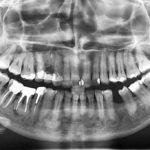

Displasia cemento-ossea nella variante florida. Case report

Florid cemento-osseous dysplasia. Case report

Viene descritto il caso clinico di una paziente affetta da displasia ossea nella variante florida in cui il sospetto diagnostico...